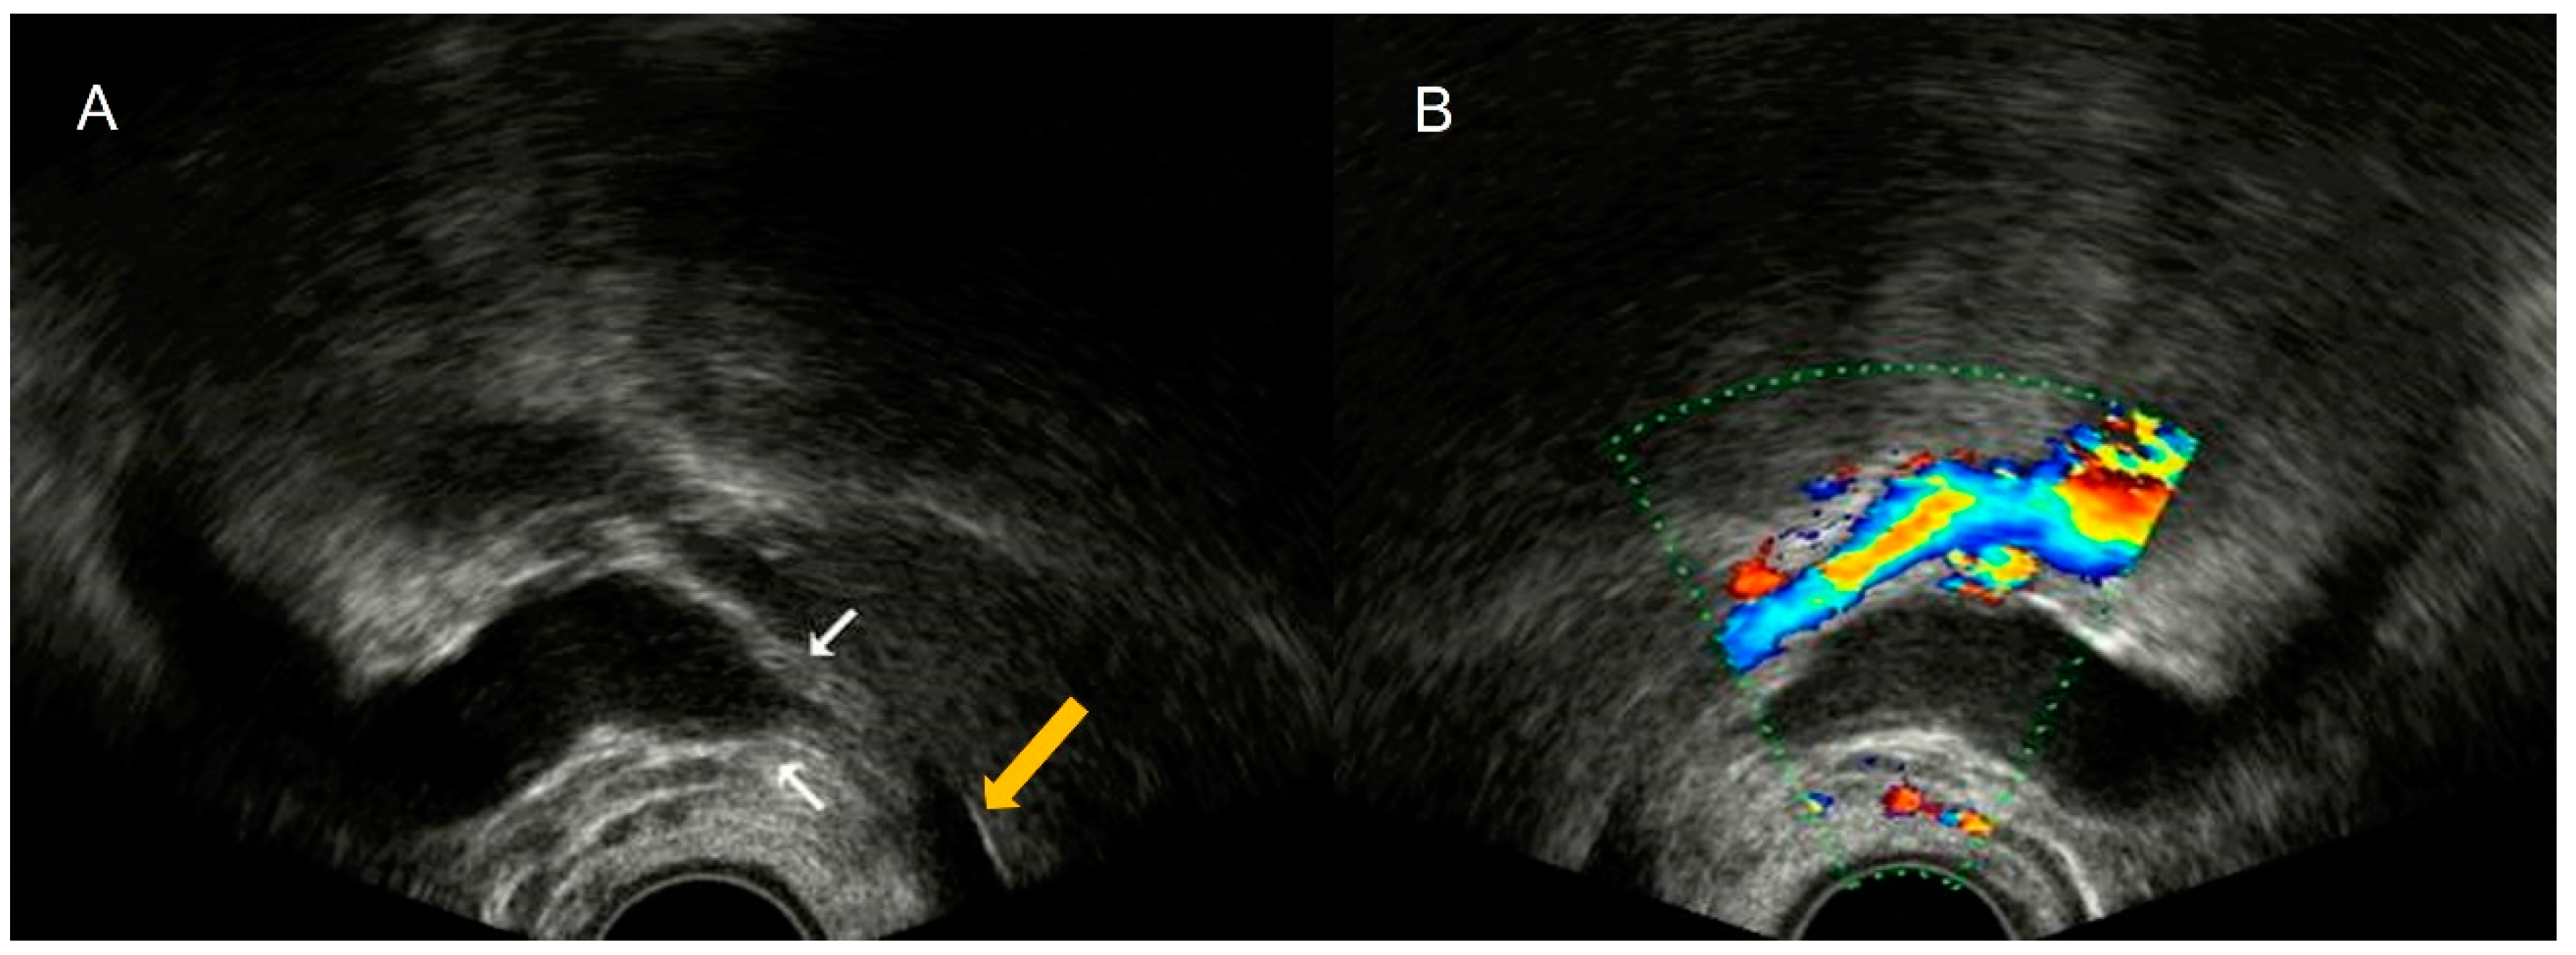

4.1. Pelvic Congestion